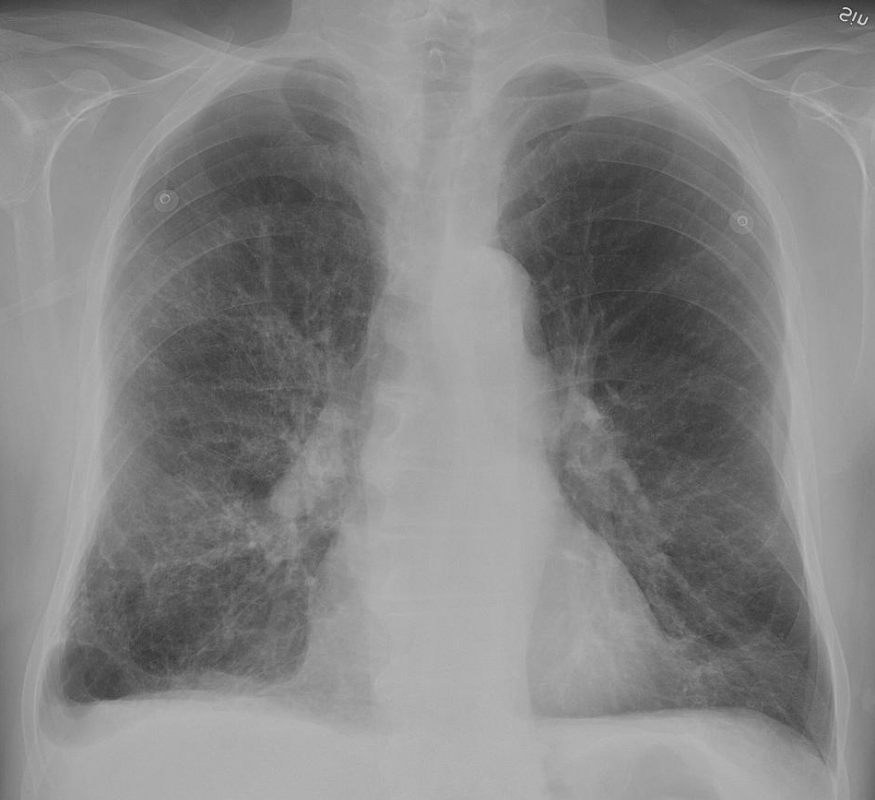

Clinical features may include initial symptoms of an upper respiratory tract infection mimicking a viral infection, usually associated with low-grade fevers. This may progress to the lower respiratory tract within a few days, with features often resembling those of wheezy bronchitis. Sputum may be difficult too expectorate and is often grey or creamy in color. The cough may persist for weeks without appropriate treatment. Many cases are diagnosed after presenting chest infections that do not respond to penicillins or first-generation cephalosporins. A chest X-ray can identify alveolar consolidation.[8]